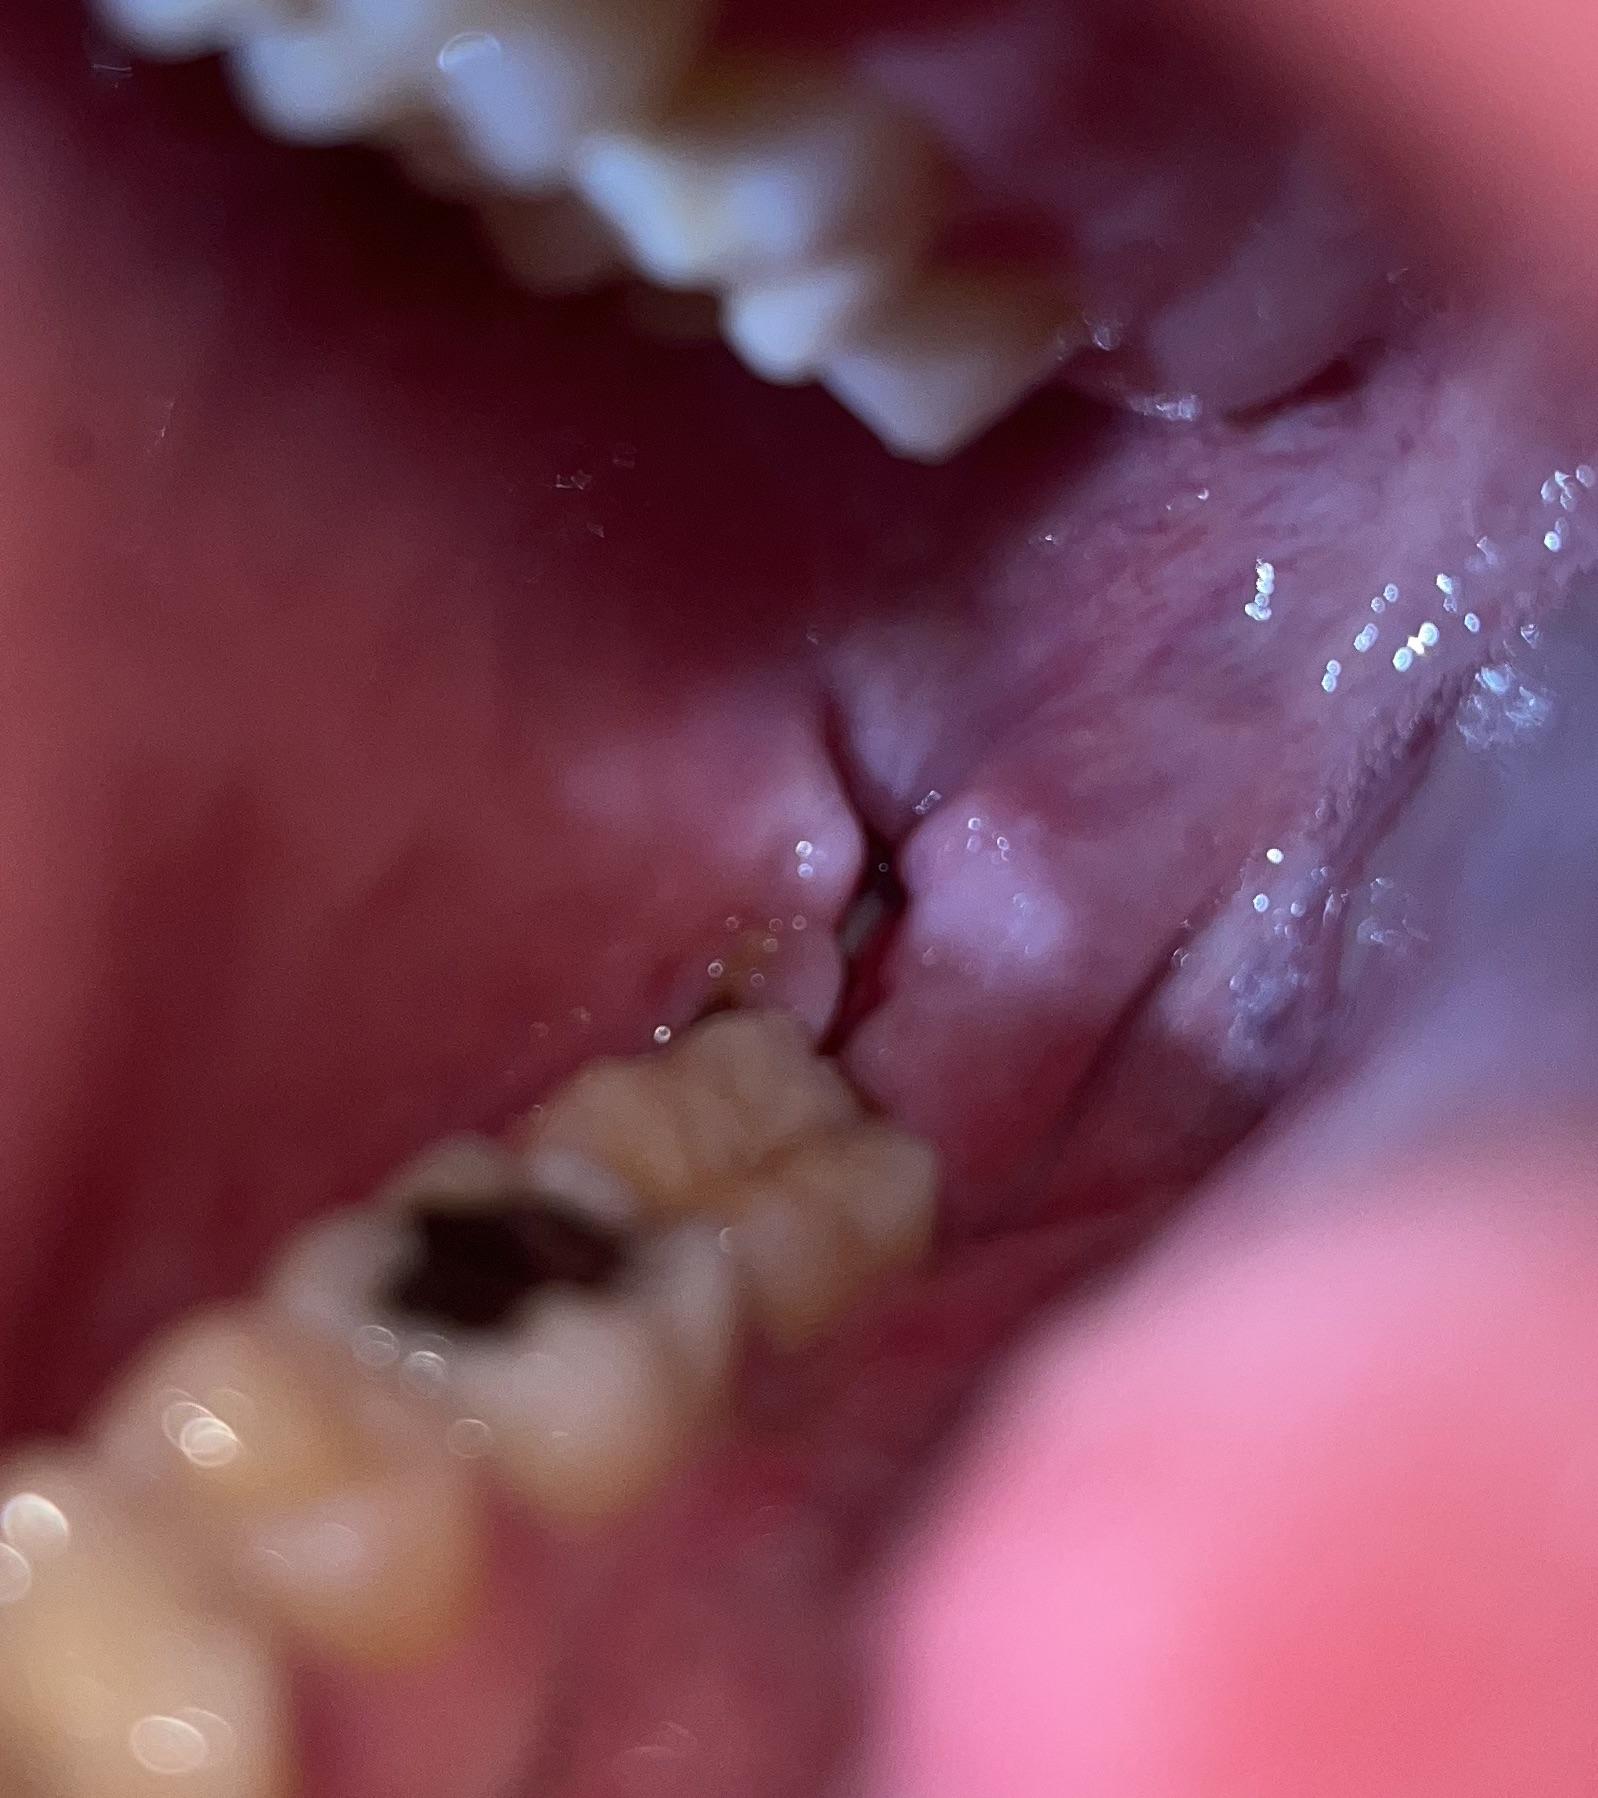

Did my stitches fall out? Should I be concerned?? r/wisdomteeth When Do Oral Stitches Fall Out They will need to evaluate the situation and determine if any further. Here’s a breakdown of the average dissolving timelines: The specific timeframe depends on various factors we discussed earlier. Despite your dentist’s skill in placing them, and your best efforts in taking precautions, you may notice that sutures (stitches) that were placed following your oral. Generally, dissolvable stitches take. When Do Oral Stitches Fall Out.